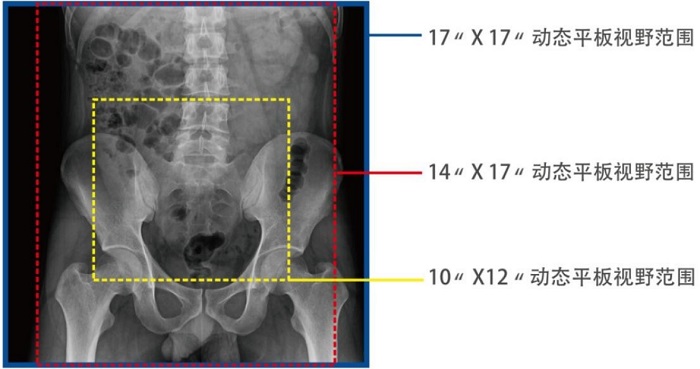

動(dòng)態(tài)DRF在肛腸科檢查中優(yōu)勢明顯。首先,17×17英寸大幅面成像,對于食道、胃、腸、結(jié)腸等大范圍成像部位,可一次曝光完成,極大減少了患者的輻射劑量和檢查時(shí)間,且空間分辨率高,與傳統(tǒng)胃腸機(jī)相比,圖像質(zhì)量大幅提升。